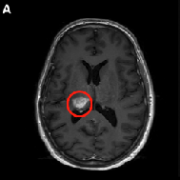

病灶多、位置深、易復(fù)發(fā),不開(kāi)顱也能“消滅”膠質(zhì)瘤,國(guó)際前沿技術(shù)LITT你知道了嗎?

看國(guó)際前沿技術(shù)激光間質(zhì)熱療如何殺滅惡性腦膠質(zhì)瘤...

激光間質(zhì)熱療(LITT)是治療原發(fā)性中樞神經(jīng)系統(tǒng)惡性腫瘤的一個(gè)有前景的進(jìn)展。隨著其使用適應(yīng)癥的不斷擴(kuò)大...